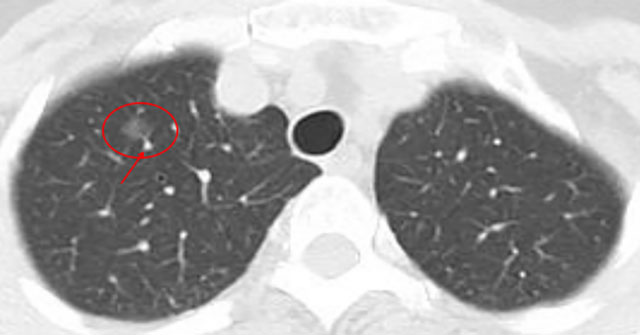

几年前,一位阿姨体检发现双肺多发10余个磨玻璃结节,最大位于右肺上叶,约9mm。当时判断:多为低风险,医生建议半年随访。

几年前影像展示与分析,5mm层厚、无薄层。

上图中红色圈原位癌可能性较大,尤其右肺上叶尖段二个结节,可见血管增粗及血管弯5mm层厚,无薄层重建;橙色圈多考虑不典型增生可能性大;黄色圈大概只是肺泡上皮增生;绿色圈考虑是良性的。